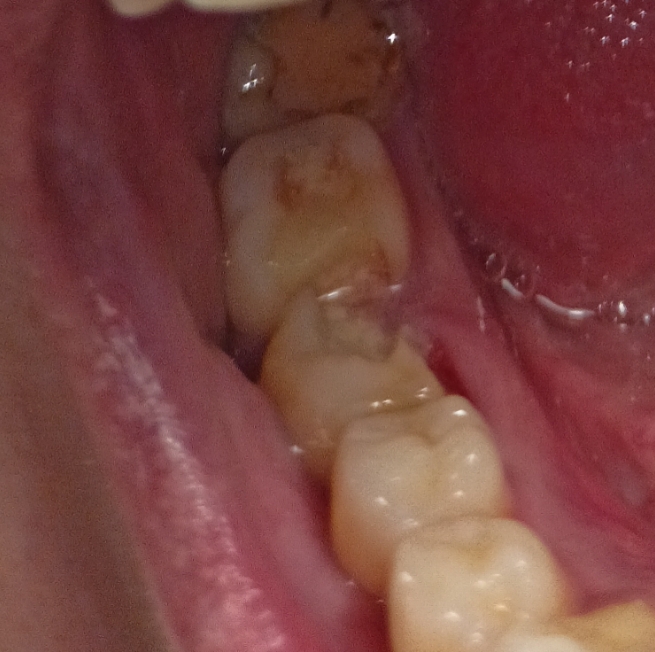

1000070960.jpg 313Кб, 1117x832

1117x832

1000070961.jpg 180Кб, 882x704

882x704

Зуб пятерка. Возможно такое вылечить, анонче? Отклолся как то, вообще не болит.

Аноним 11/08/25 Пнд 15:56:42 1635620 36